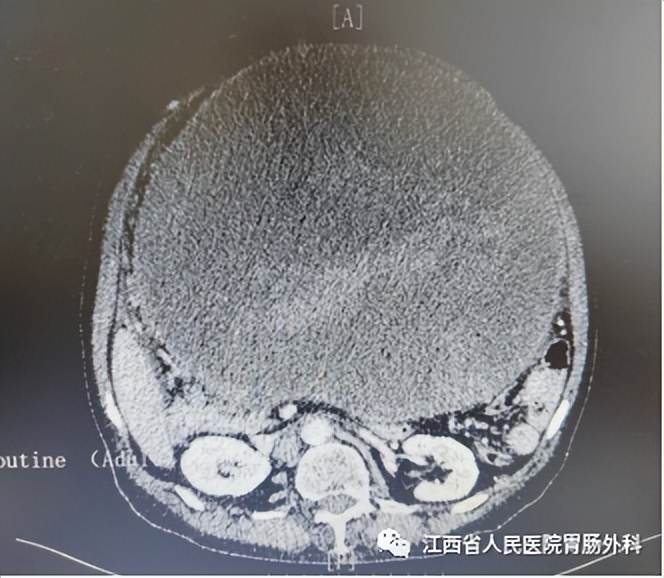

入院后完善相关检查:血红蛋白:82g/L;CA125:127.8U/ml;白蛋白 33.7g/L。腹部CT:腹腔巨大占位(图2),考虑来源于胃体间质瘤可能;脾大;腰2、3、4椎体失稳;头颅+腹部MR:腹腔内巨大囊实性占位,考虑胃来源间质瘤可能(图3);右侧颈内动脉未见显影,考虑闭塞可能性大,左侧颈内动脉多发结节状突起。术前诊断:1.胃恶性肿瘤(巨大间质瘤?),2.高血压3级(极高危组),3.中度贫血,4.右侧颈内动脉闭塞,5.脾大,6.腰椎不稳定。

图2(术前CT)